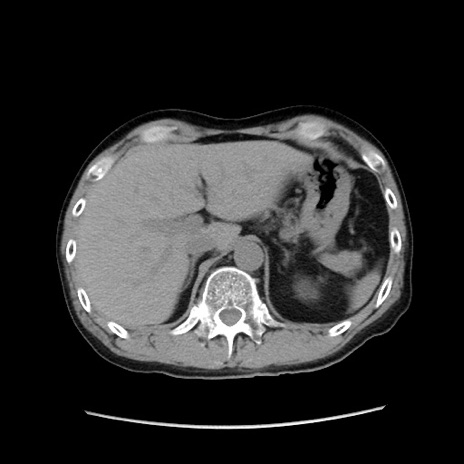

症例37(横断像)

【症例】40歳代 男性

【主訴】腹痛

【現病歴】4時間ほど前に電車に乗車中に臍部上より腹痛出現。徐々に増悪し起立困難となり、救急外来受診。生ものは数日食べていない。今朝お雑煮を食べた。

【身体所見】BT 36.8℃、BP 117/84mmHg、HR 91/min、SpO2 97%、苦悶様、腹部:臍上部広範囲圧痛あり、反跳痛±

【データ】WBC 8100、CRP 0.03